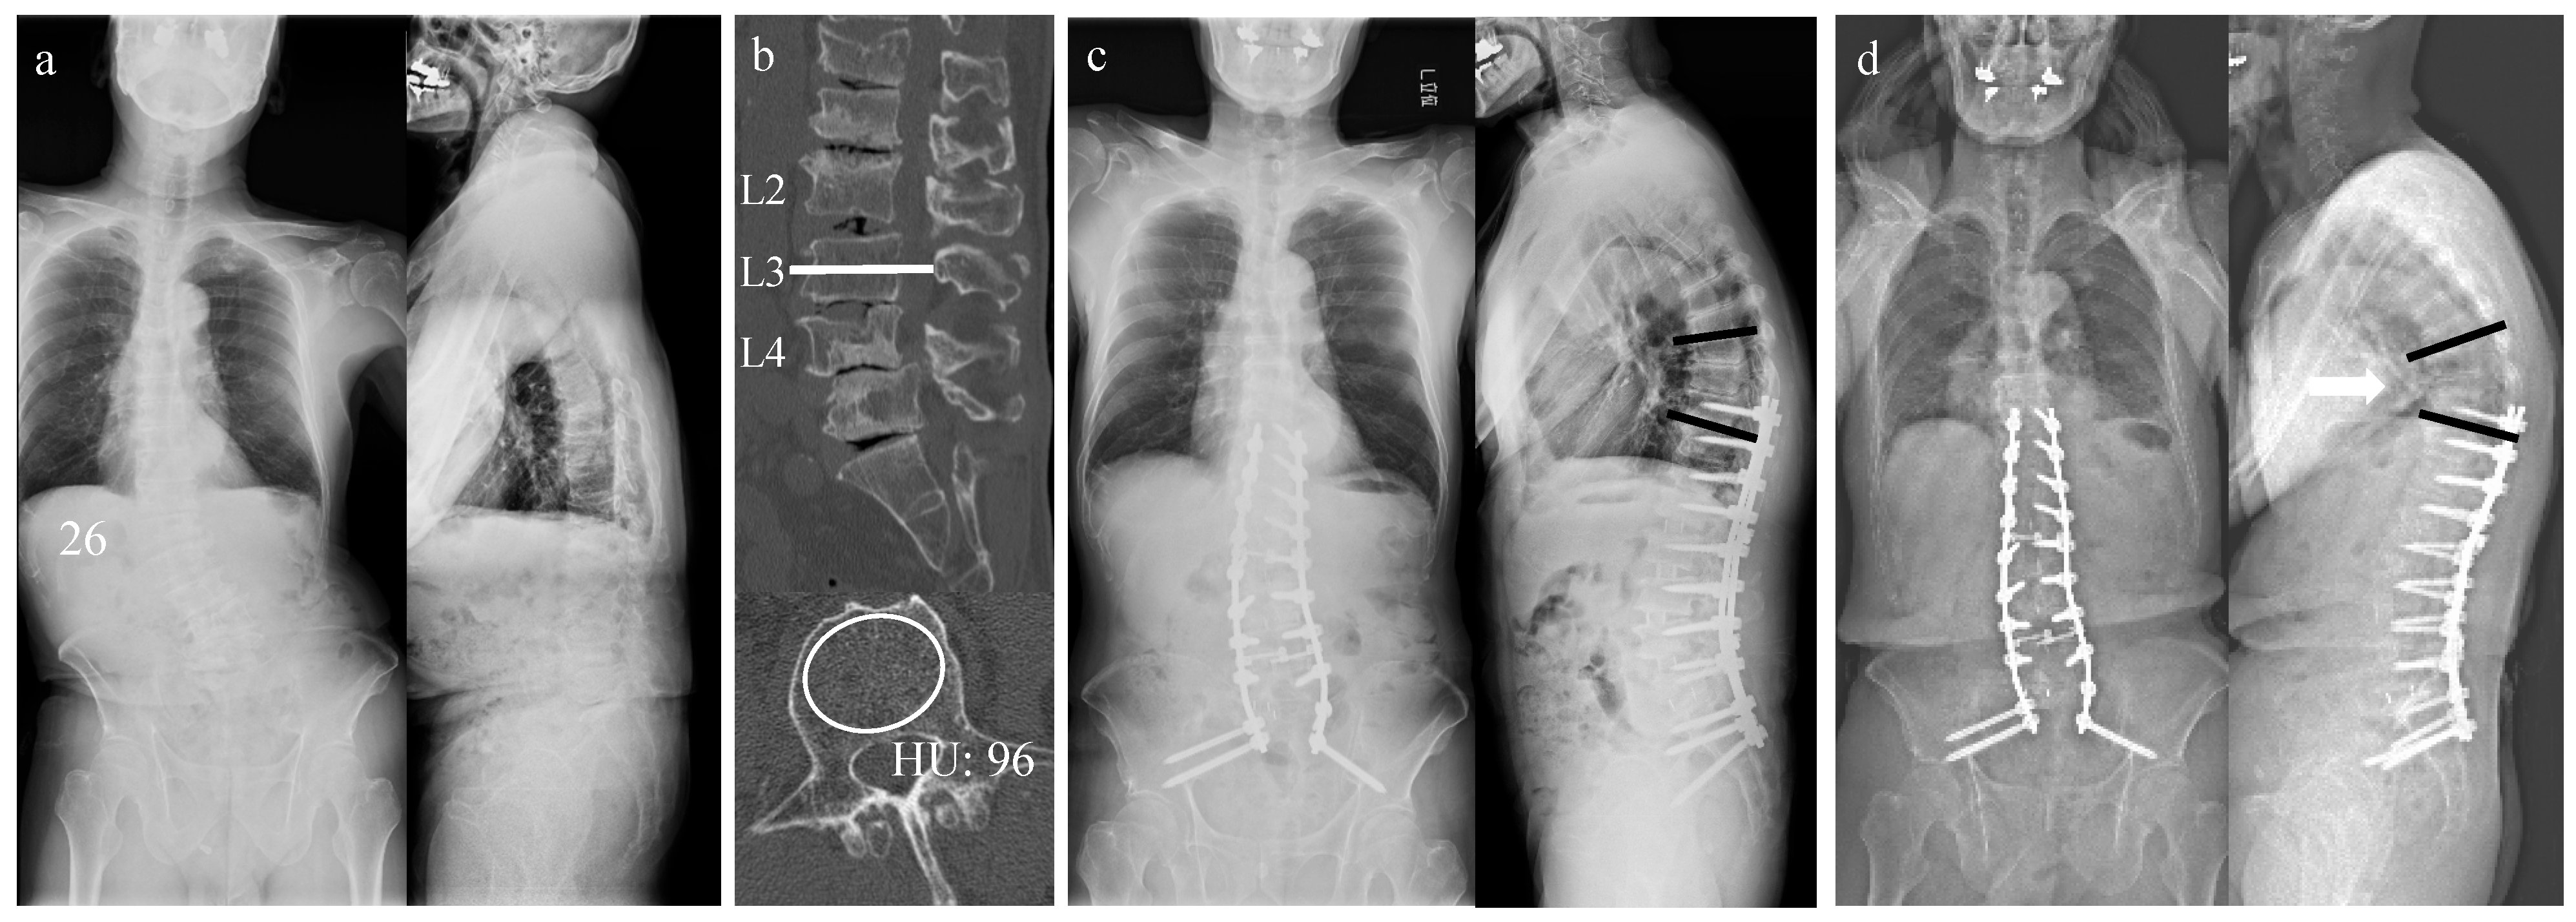

3.5. Case Presentation